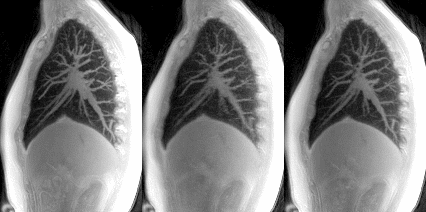

Flow-volume maps produced by 3D MR spirometry